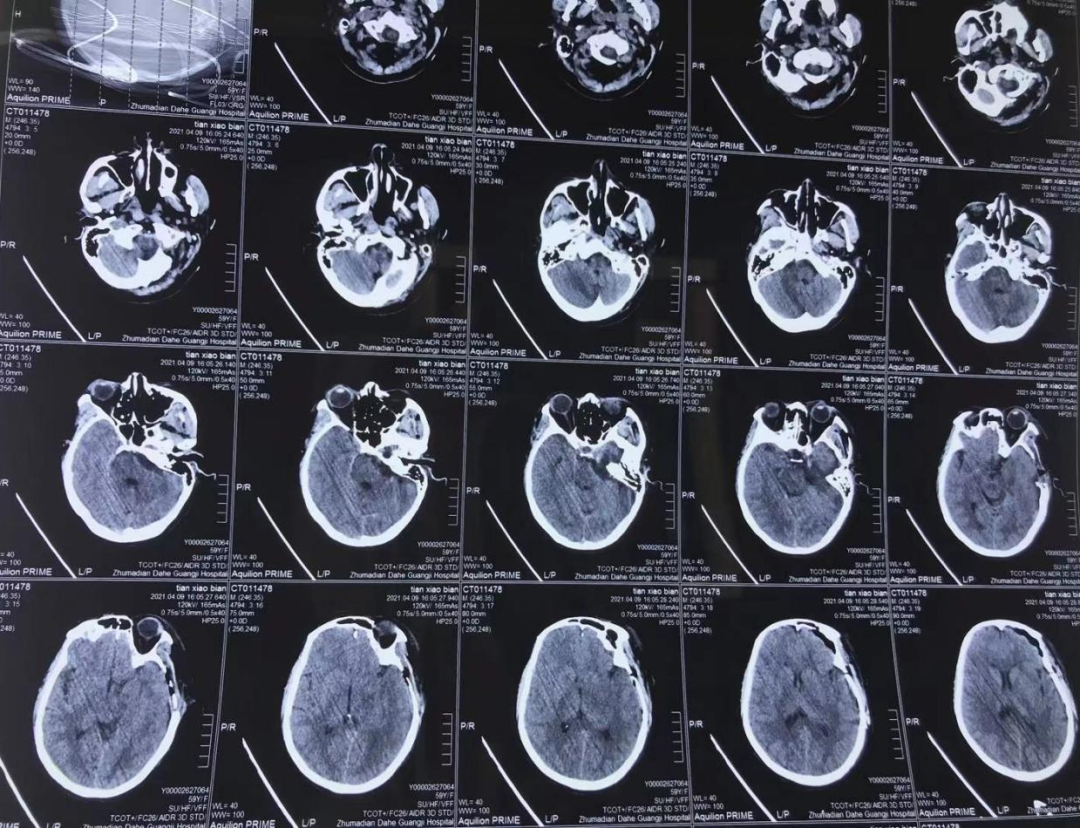

術(shù)后檢查: